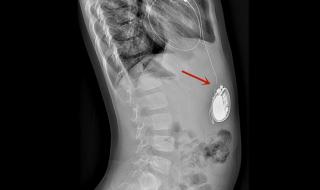

全磁浮人工心脏介绍 男子植入最小人工心脏

全磁浮心脏即离心泵人工心脏,被称为第三代人工心脏,是目前最先进,对人体影响最小也是最耐用的人工心脏,美国FDA前两年刚上市了第一款,我国高端医疗器械几乎无国产产品。